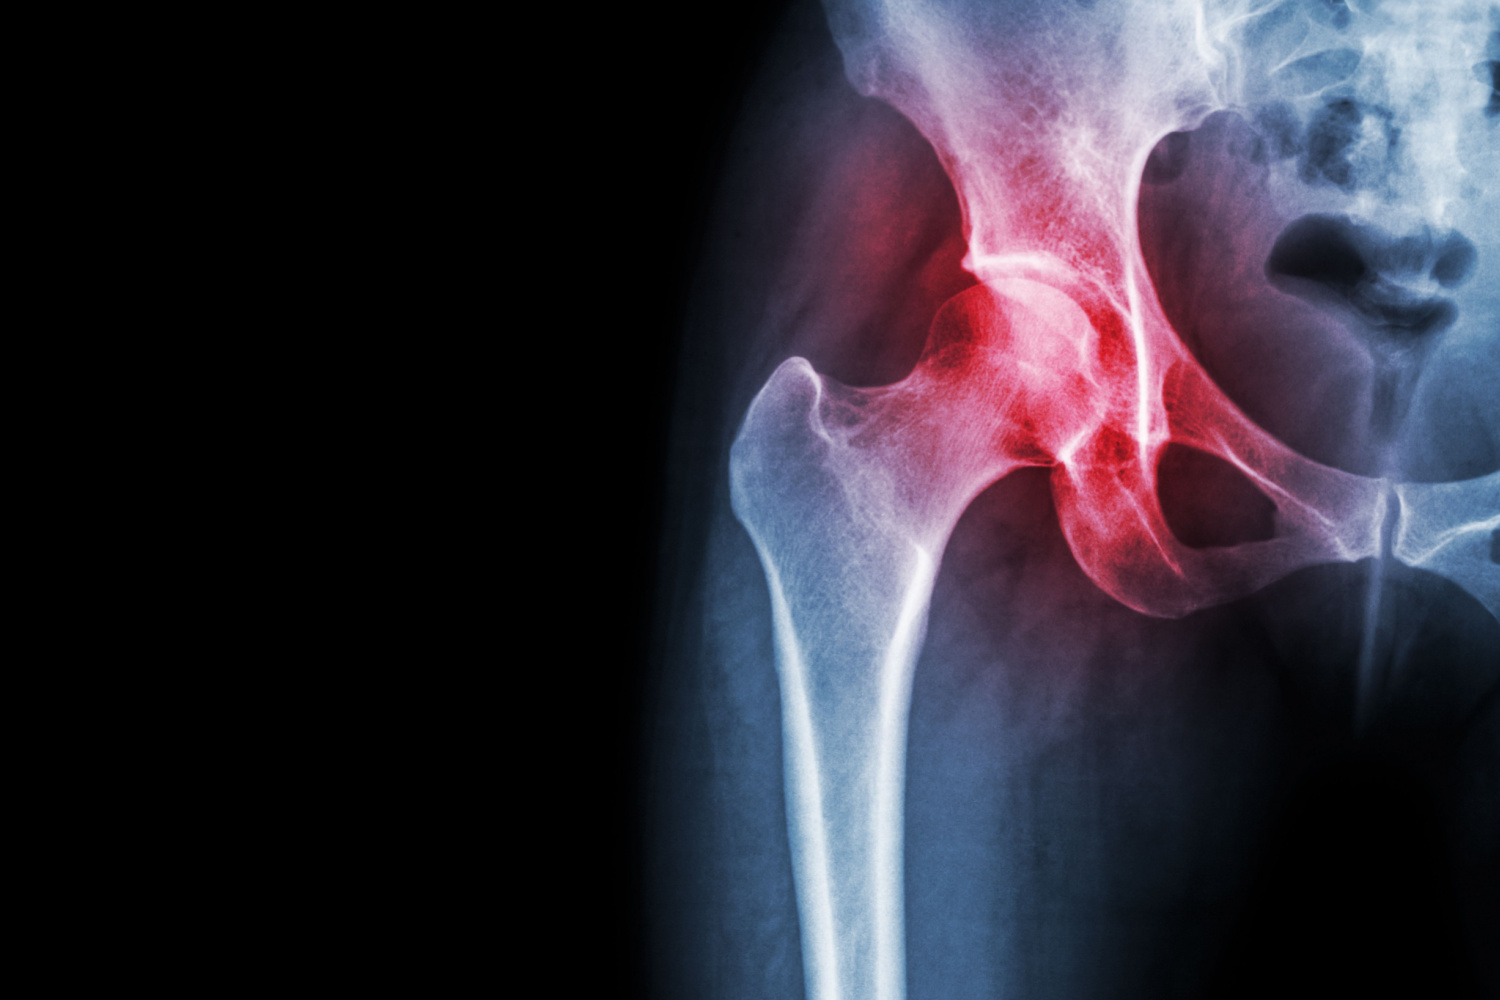

Некроз тазобедренного сустава: Фотографии и особенности лечения